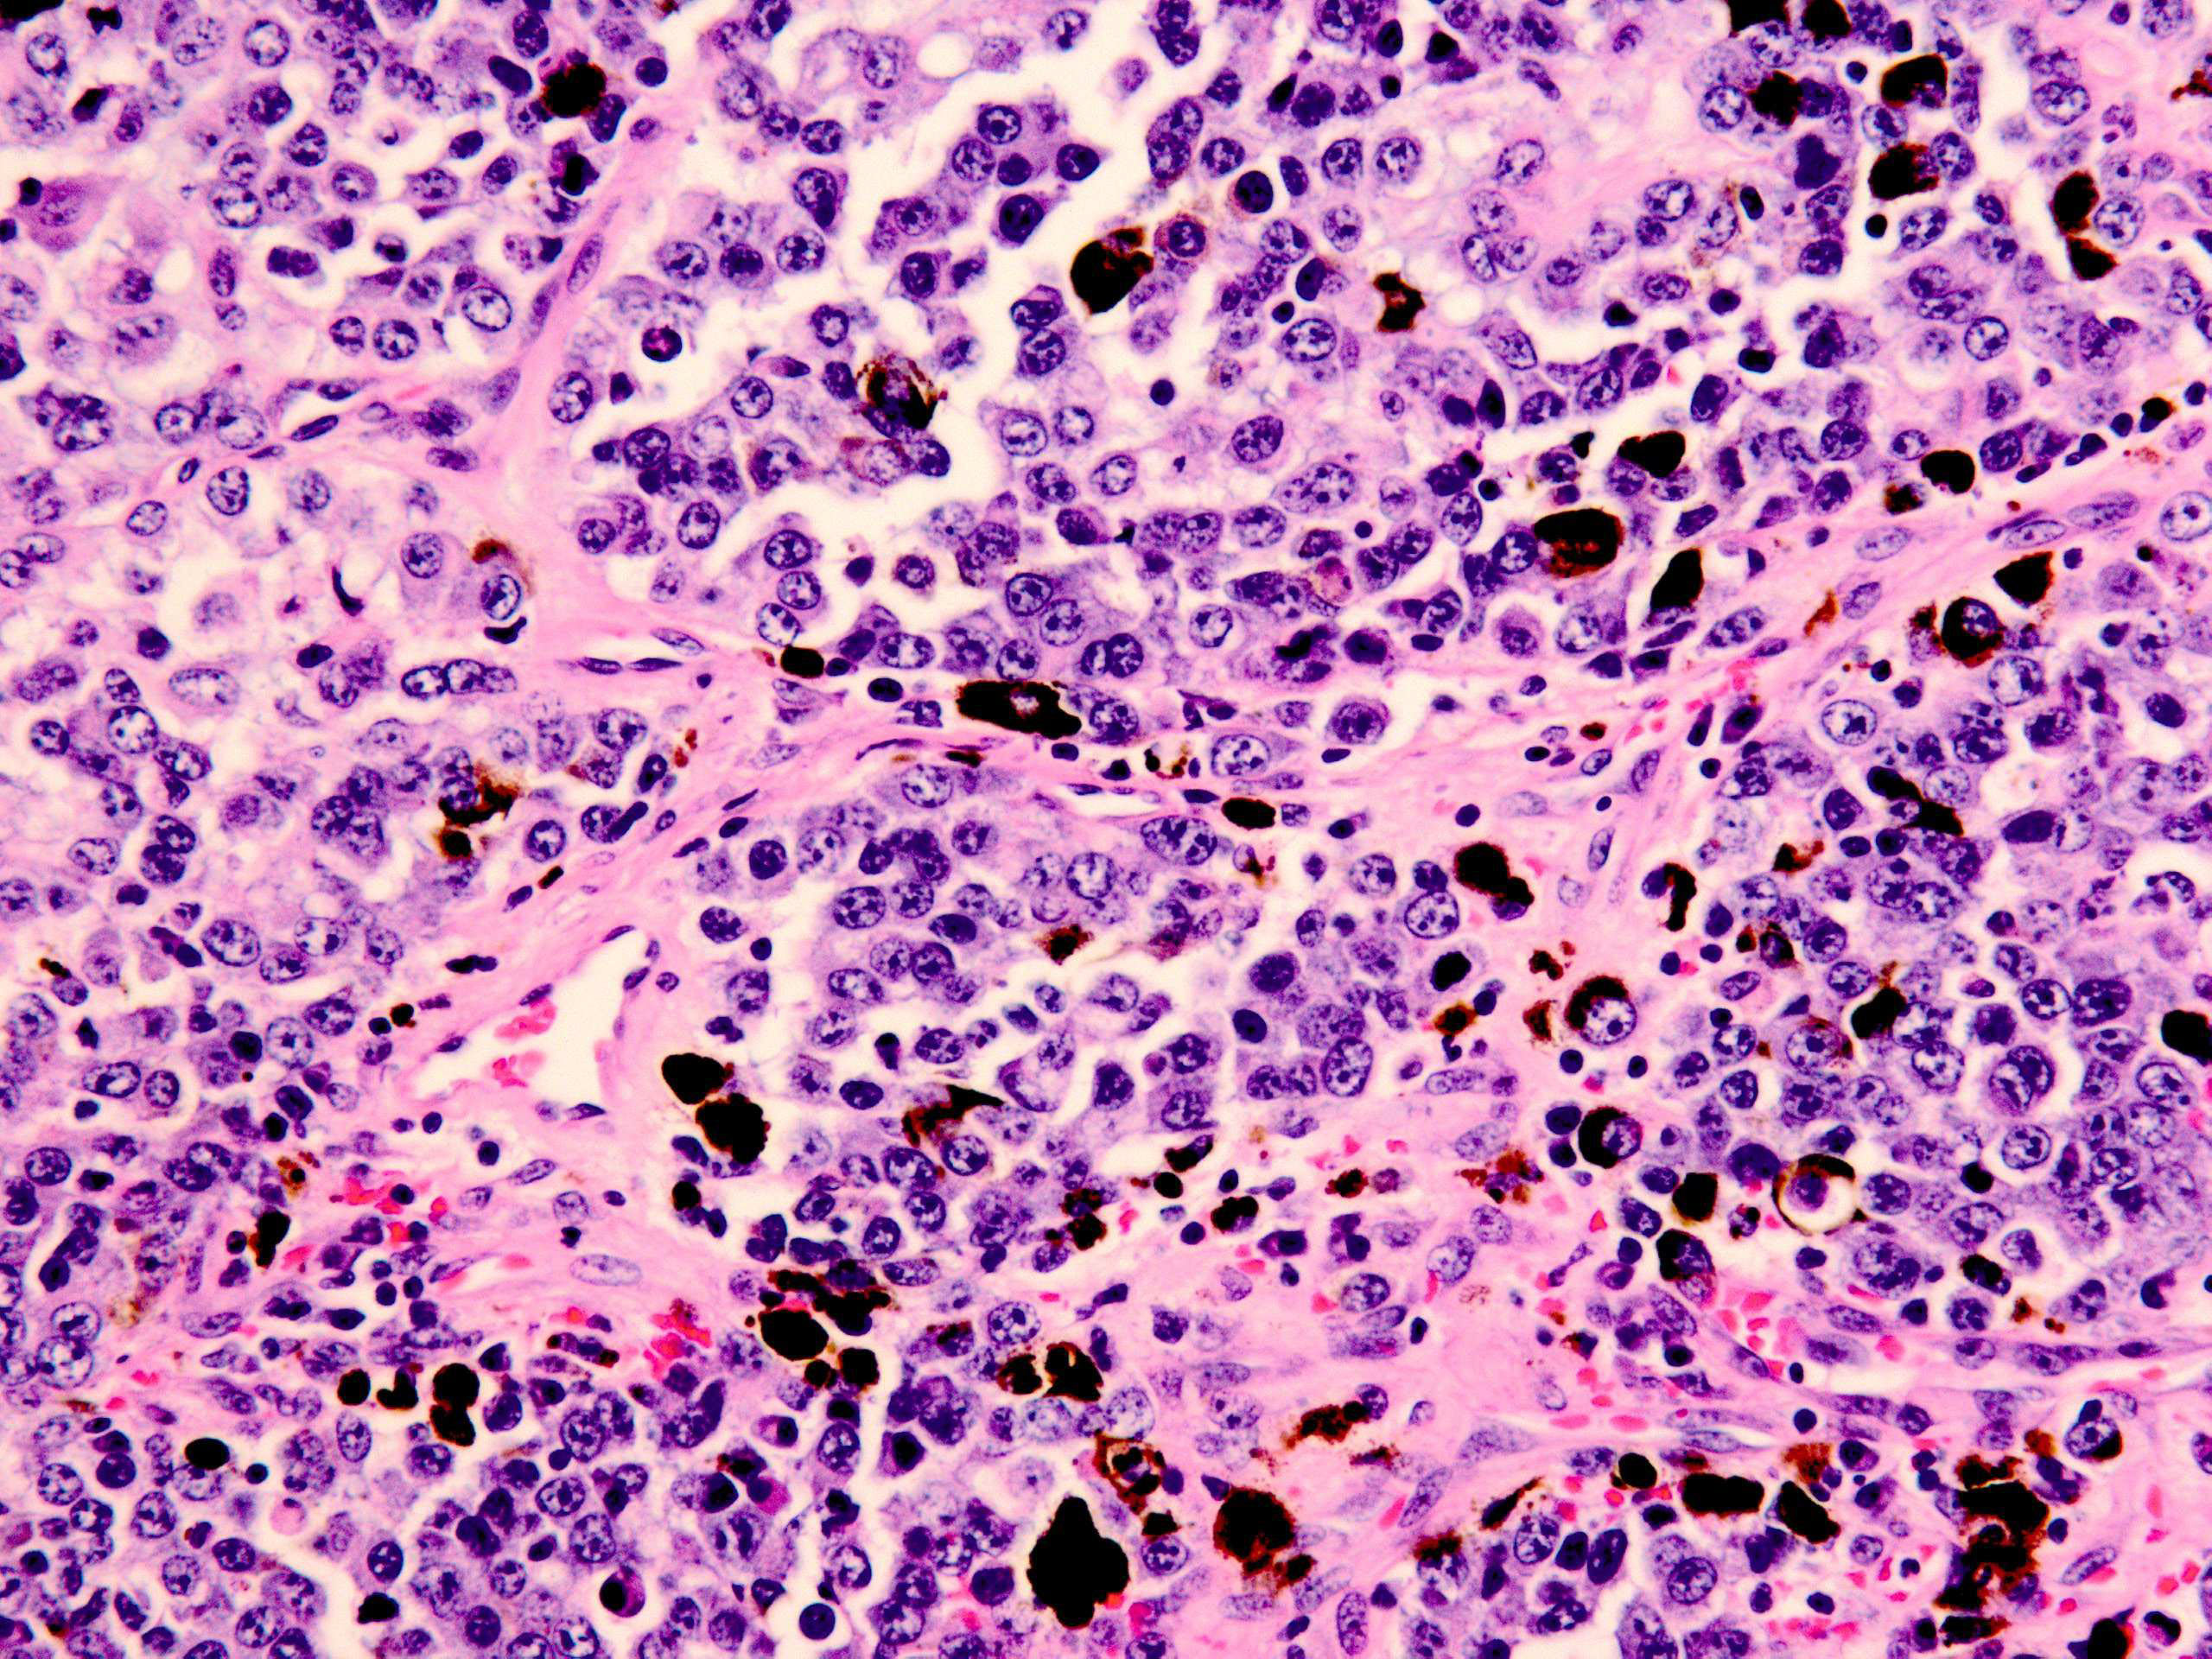

黒色腫は、皮膚のメラノサイト細胞で発生する皮膚がんの一種です。他の種類の皮膚がんに比べて発生頻度ははるかに低いですが、進行性が高く、体全体に広がる可能性が高くなります。